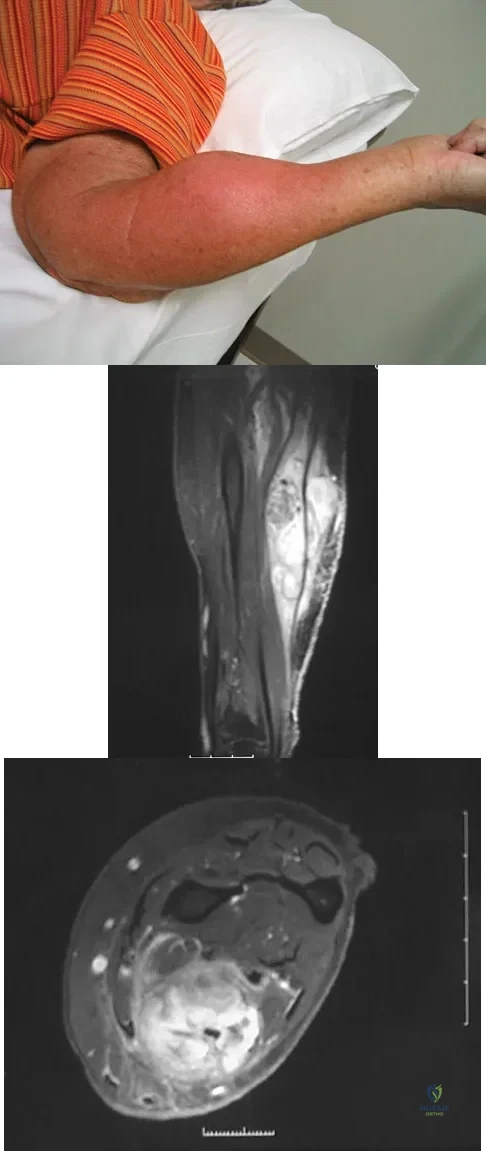

Figure 8a shows the clinical photograph of an 83-year-old woman who has an enlarging left forearm mass. MRI scans are shown in Figures 8b and 8c. What is the next most appropriate step in management?